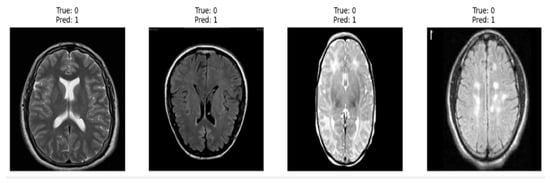

3.2. Dataset Description

The BR35H dataset from Kaggle [36] consists of 3000 pre-labeled MRI brain scans, equally divided into 1500 tumor images and 1500 normal samples. This dataset has been widely utilized for supervised learning and classification tasks. A detailed overview of the dataset, including representative samples of benign and malignant MRI images, is presented in Table 1. However, a key limitation of the BR35H dataset is that it provides images only at the slice level, without metadata regarding the number of unique patients. Consequently, each MRI slice was treated as an independent data point during model development.